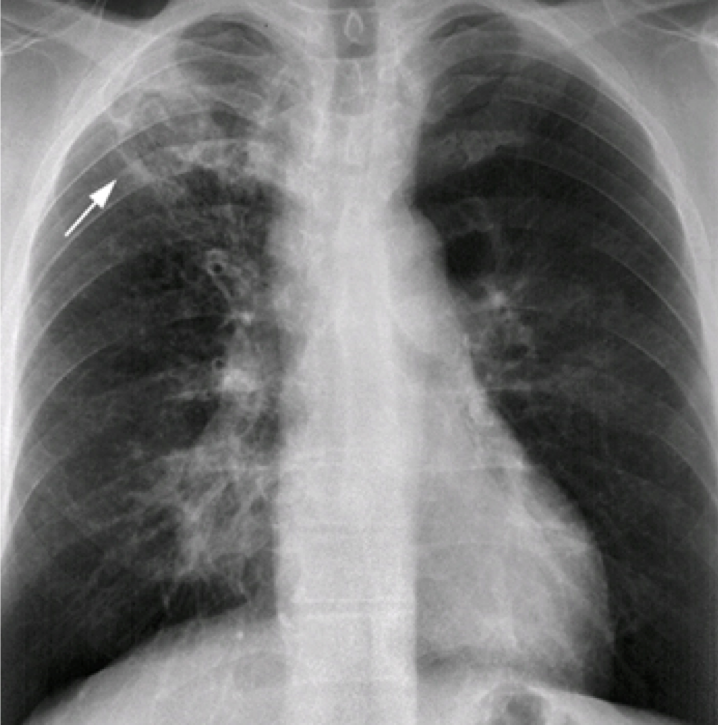

Question 8

Question

In what disease will you see this in?

Answer

• COPD

• Pneumonia

• Epiglottitis

• Croup

• Retropharyngeal Abscess